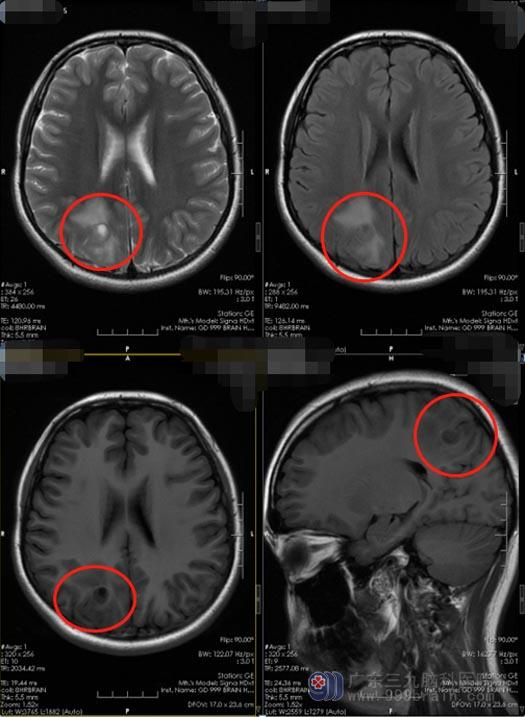

在福建漳州某三级医院,头颅MRI检查发现右侧枕叶有一结节病灶,考虑炎性肉芽肿。炎性肉芽肿是由细菌、真菌、寄生虫感染及异物致病因子刺激,引起的巨噬细胞增生所形成的境界明显的结节状病灶,可以刺激脑细胞出现异常放电,导致癫痫发作。医生对她进行了中药治疗。

来到广东三九脑科医院神经外五科,鲁明主任接诊了小玲。详细询问病史和阅读MRI片子后,发现小玲的颅内病变位于枕叶,约鸭蛋大小。

枕叶为视觉皮质中枢,枕叶病损时不仅发生视觉障碍,而且还会出现记忆缺陷和运动知觉障碍等症状。虽然小玲的视力还没有受到影响,但是应尽快地进行手术治疗,征得小玲及父亲母亲的同意, 2020月11月18日,鲁明主任主刀为小玲行“右侧枕叶占位病变切除术”,术后小玲恢复良好,四肢活动自如,病理报告提示:节细胞胶质瘤,WHOⅠ级。